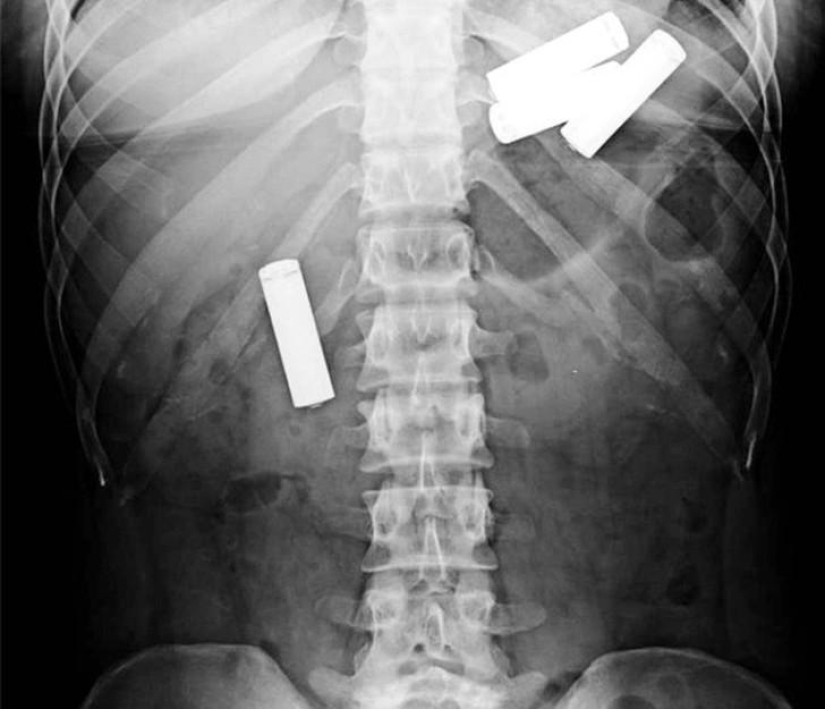

And here are the batteries!